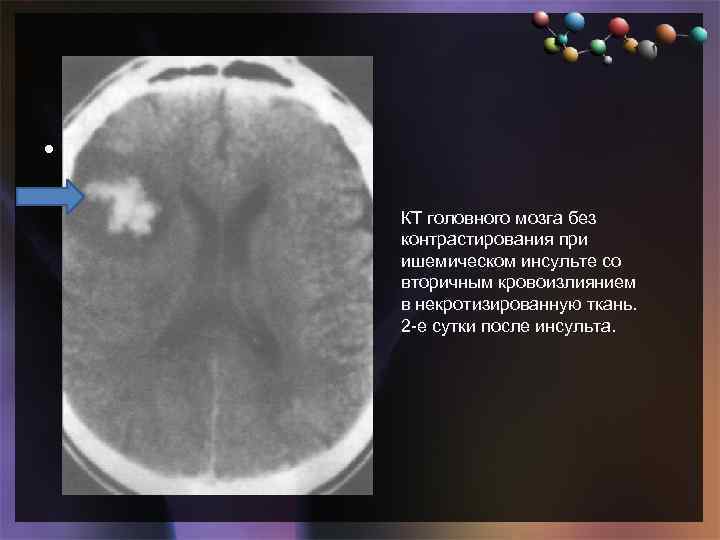

• Подзаголовок слайда КТ головного мозга без контрастирования при ишемическом инсульте со вторичным кровоизлиянием в некротизированную ткань. 2 -е сутки после инсульта.

• Подзаголовок слайда КТ головного мозга без контрастирования при ишемическом инсульте со вторичным кровоизлиянием в некротизированную ткань. 2 -е сутки после инсульта.